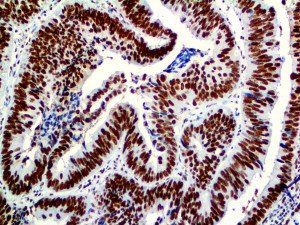

The first cytokines released are interleukin 1β (IL-1β) and tumor necrosis factor-α (TNF-α), which attract a variety of circulating white blood cells (WBCs) to the infection site, including neutrophils, monocytes, macrophages, and natural killer (NK) cells. This response, along with the antipathogenic chemicals released by these cells (i.e., complement), comprise the innate immune response. These cells directly attack the invading pathogen and also release additional cytokines, chief among them interleukin-1 and 6 (IL-6). IL-6 is essential for invoking the adaptive immune response, which calls T-cells, B-cells, and T helper (Th) cells to the infection site. IL-6 also stimulates further recruitment, proliferation and activation of macrophages.

It is the ICU physician who is most likely to witness one of the deadliest manifestations of the abnormal immunological response, the cytokine storm syndrome (CSS). This response is also referred to by some as the cytokine release syndrome (CRS). CSS is characterized by continuous activation and expansion of macrophage and lymphocyte populations, which secrete large amounts of cytokines, causing the cytokine storm. This massive cytokine release is akin to hemophagocytic lymphohistiocytosis (HLH) disease, a syndrome characterized by initial unchecked and persistent activation of cytotoxic T lymphocytes and NK cells.

This activation induces inflammatory monocytes to highly express IL-6, starting a localized and then systemic cascade effect that results in hyperproduction of IL-6, which accelerates the inflammatory process. Because IL-6 also increases vascular permeability, excessive levels cause blood vessels to become very leaky. This, along with clotting factors released from vascular endothelial cells, stimulates the coagulation cascade, resulting in microthrombosis (tiny clots), which leads to ischemia and tissue death of the kidney, intestines, heart, liver, brain and extremities.